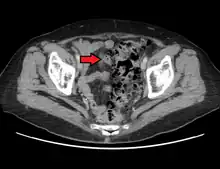

Imaging

- Contrast CT is the investigation of choice in acute episodes of diverticulitis and where complications exist.